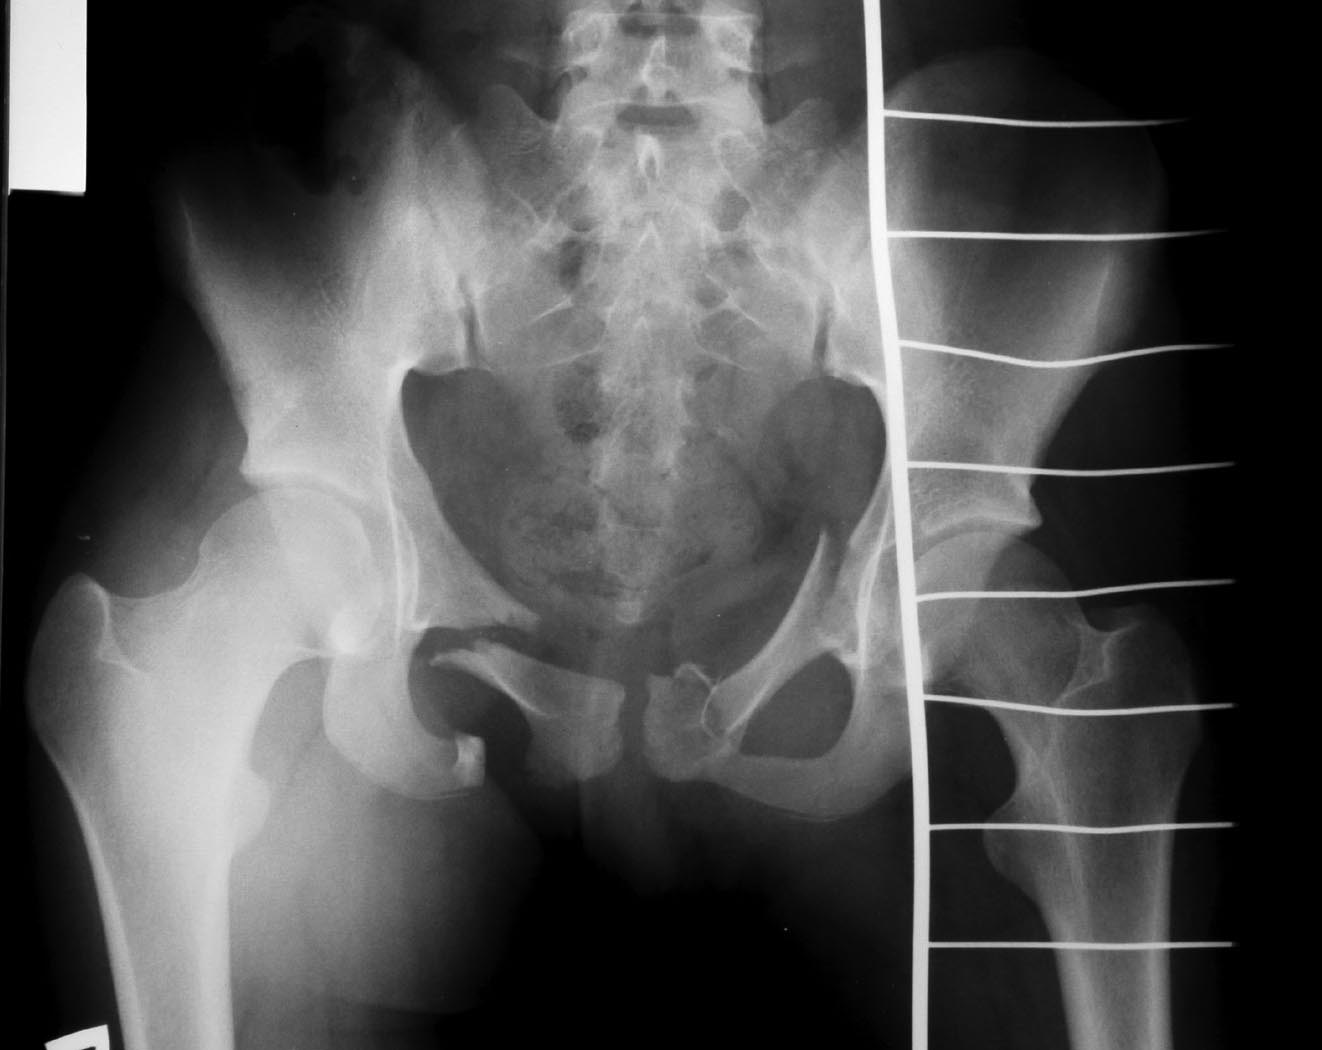

Девочка 14 лет, ДТП - наезд автомобиля. СГМ, ушиб левого легкого, переломы костей таза. Помогите, пожалуйста, определиться с тактикой лечения переломов таза!

Дообследование таза рентгенологически. Из анамнеза уточнить механизм - боковое сдавление слева?!

Пат анатомия: перелом лобковых и седалищных костей с обеих ст орон, разрыв лобкового симфиза,

перелом боковых масс крестца слева?! Уточнить по серии рентгенограмм: подвздошная, запирательная

(исключить трансвертлудный перелом) каудальная (задний отдел таза). КТ очень полезно.

Из оперативного пособия: пластина - остеосинтез лобковой кости справа, симфиза и медиального перелома

лобковой кости слева. Латеральный перелом лобковой кости - винт 3,5 мм, спица с нарезкой, просто спица. (по

мере эффективности убывают), фиксация боковых масс крестца слева, если есть перелом. При наличие повреждений

передних крестообразных связок возможно с обеих сторон или сочетание свзки справа + боковые массы слева - фиксация КПС с обеих сторон.

Крестцово-копчиковый отдел внимательно посмотреть - можно не оперировать, но учесть при активизации.

Аппарат - не самый лучший вариант, нужна анатомическая репозиция симфиза и лобковых костей, стабилизация боковых масс крестца. Тогда можно говорить об активном послеоперационном ведении. Репозицию начинать с переднего отдела, Транс КПС винта в последнюю очередь - положение больной на спине.

Справа интерпозиция, левая половина таза развернута кнаружи.

Добрый день! по представленной рентгенограмме можно определить как минимум билатеральное ротацинно нестабильное повреждение тазового кольца. справа латеральная компрессия слева "открытая книга" в целом "деформация качения". КТ - золотой стандарт, проясняющий все детали повреждения, если нет КТ - полипроеционная рентгенография, как указано выше.ОБЯЗАТЕЛЬНО - ретроградная статическая цистография минимум в прямой и каудальной проекциях, если есть возможность КТ с контрастированием пузыря. Справа интерпозиция есть и скорее всего стенкой мочевого пузыря ( в своей практике имеем несколько пациентов с подобными повреждениями). при этом макрогематурии может и не быть. В своей клинике применяем следующую тактику: